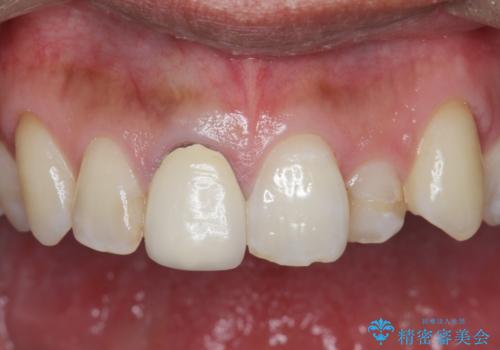

前歯の並びが改善し、色調の気になっていたクラウンの審美性も大きく改善することができました。

奥に位置している前歯を部分ワイヤー矯正ののちマウスピース矯正インビザラインで並べ、矯正治療後に審美的なジルコニアクラウンを作製していきます。